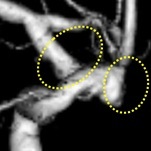

脳動脈瘤・くも膜下出血

くも膜下出血の原因となる脳動脈瘤の治療を、直達手術、血管内治療を用いて行います。

近年では、動脈瘤ができた部位の血管内に、

フローダイバーターとよばれる血流改変ステントを

留置して、動脈瘤の血栓化を促す治療も行います。

当院でも施行可能です。

フローダイバーター留置術(血管内治療)

治療前(血管造影画像) 治療後(血管造影画像)

複雑な形状の動脈瘤を認め、フローダイバーターを留置し、動脈瘤の消失を確認しています。